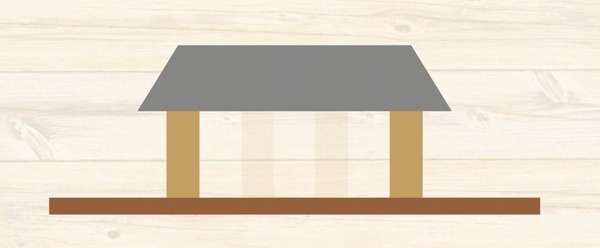

ところが

歯を支えている骨

家をイメージすると

柱を支えている地盤

1本1本の柱を支える地盤しか

もともとないわけです。

ブリッジ治療をした場合には

その歯の根っこの周囲の地盤には

本来受ける何倍もの力が実はかかっています。

つまり

地盤沈下が起こってしまうのです